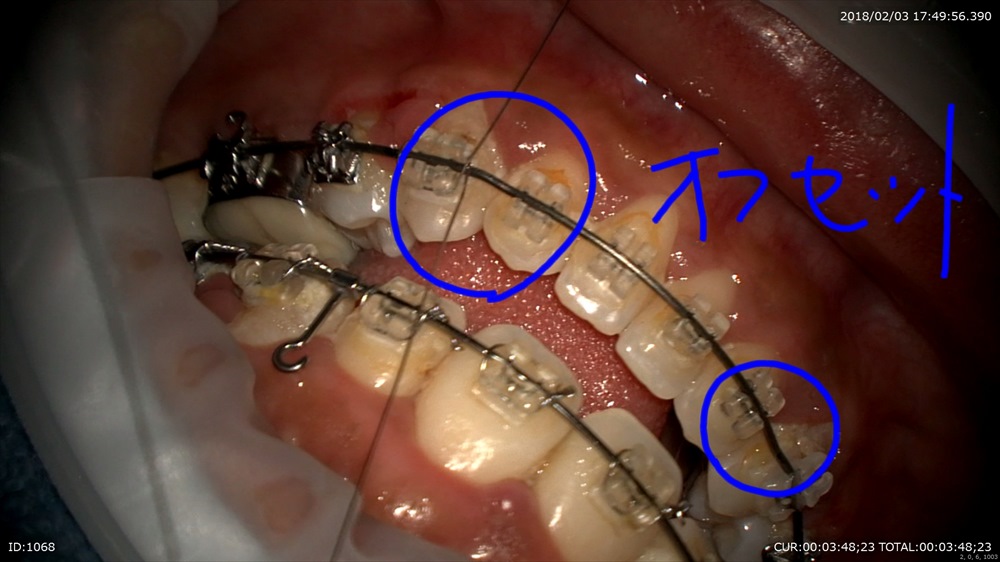

今日最後の患者さまは矯正治療

フィニッシィングステージ

犬歯が甘いので オフセットを。

この様にマイクロスコープを使用して無痛かつ丁寧な治療が当院では可能です。埼玉、八潮、草加、三郷で矯正治療ならBiVi歯科・矯正歯科まで。